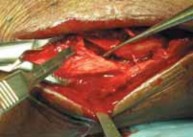

TECHNIQUES B TECH FIG 5 • Direct posterior plating is well

suited for fractures involving large portions of the posterior malleolus.

A.

Postreduction lateral radiograph showing a posterior malleolus fracture involving more than one third of the articular surface.

B.

Patient in prone position, incision between Achilles and posterior fibula border.

C.

Access is via the interval between the flexor hallucis longus and the peroneal muscle belly. D. Posterior malleolar fragment following A D fibular plating. POSTERIOR MALLEOLUS FIXATION 1. If an adequate reduction can be achieved via closed, indirect reduction, the fracture can be stabilized with cannulated lag screws placed in the anterior-to-posterior direction.